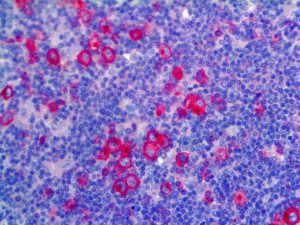

It is the ICU physician who is most likely to witness one of the deadliest manifestations of the abnormal immunological response, the cytokine storm syndrome (CSS). This response is also referred to by some as the cytokine release syndrome (CRS). CSS is characterized by continuous activation and expansion of macrophage and lymphocyte populations, which secrete large amounts of cytokines, causing the cytokine storm. This massive cytokine release is akin to hemophagocytic lymphohistiocytosis (HLH) disease, a syndrome characterized by initial unchecked and persistent activation of cytotoxic T lymphocytes and NK cells.

Clinical and laboratory manifestations of HLH include fever, enlarged liver and/or spleen, neurologic dysfunction, coagulopathy, liver dysfunction, cytopenias (i.e., low levels of erythrocytes, leukocytes, and/or platelets), hypertriglyceridemia, hyperferritinemia, hemophagocytosis, and eventually diminished NK cell activity as the immune system becomes progressively paralyzed. HLH can be familial (primary HLH) or secondary to another disease process (sHLH), such as rheumatic disease, in which it is referred to as macrophage activation syndrome (MAS, characterized by elevated ferritin).